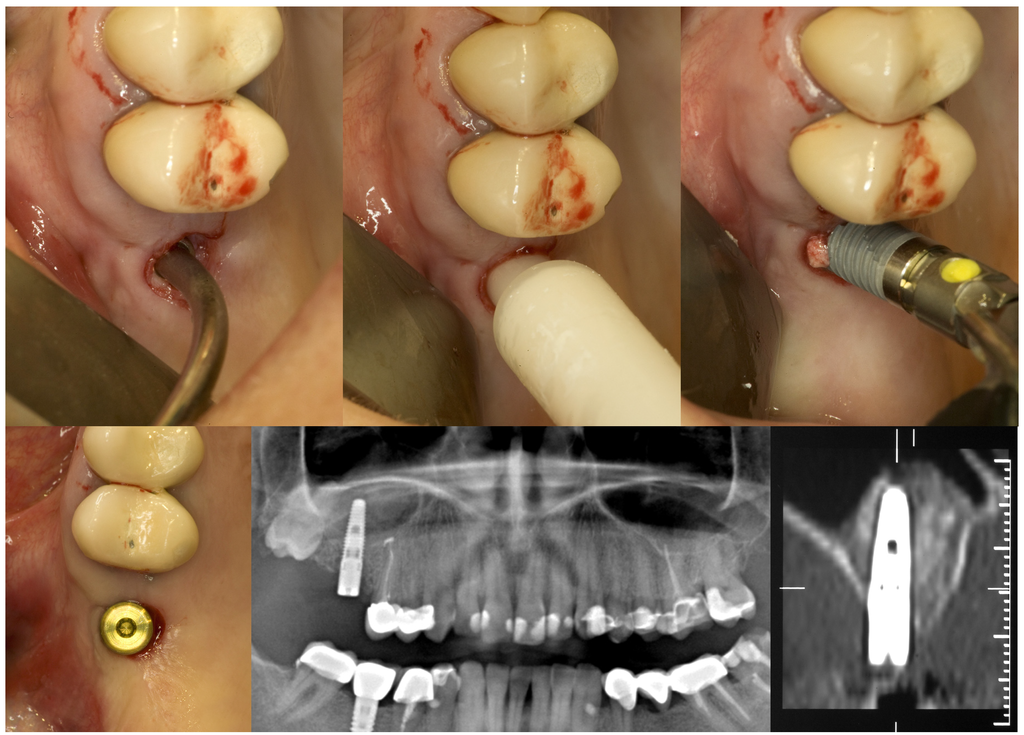

Figure 2.

GPT and implant placement in the right upper first molar region of a 43-year old woman.